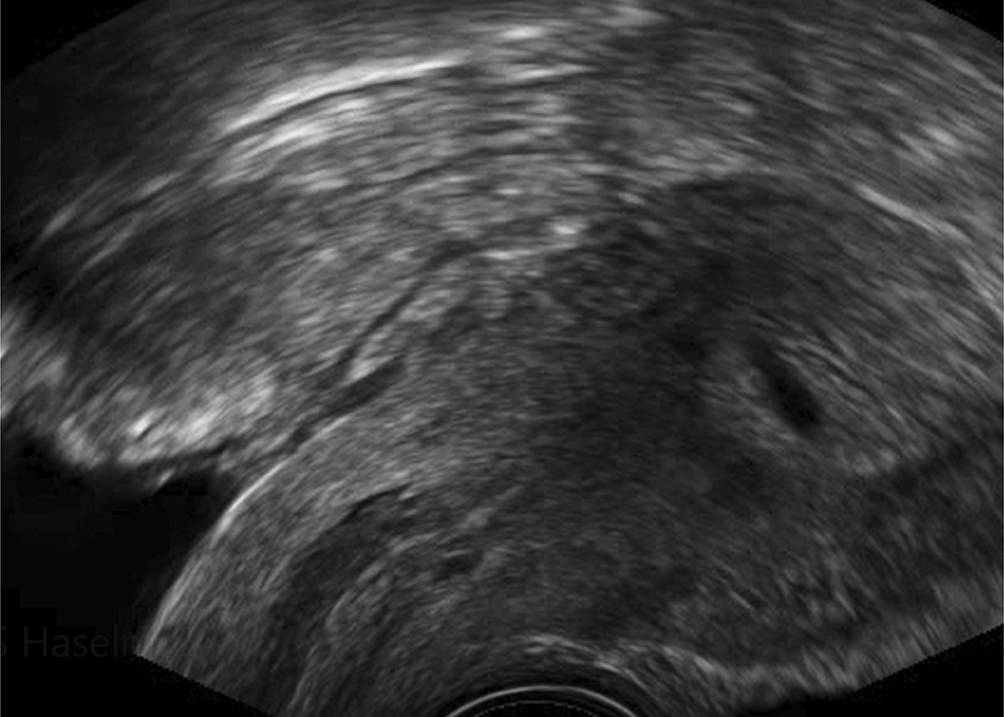

Beim „blob“ zeigt sich eine inhomogene, meist nicht an allen Seiten scharf abgegrenzte Struktur, die nicht dem Ovar und dem Uterus zugeordnet werden kann (58 % aller Fälle; Abb. 2). Schon etwas weiter ist eine Schwangerschaft, die sich als „bagel“ zeigt und wo im Zentrum der „blob“-Struktur ein leerer Fruchtsack gesehen werden kann (21 % aller Fälle; Abb. 3). Den Fruchtsack mit darin erkennbaren embryonalen Anteilen sah man in einer Metaanalyse in 13 % der Fälle, bei denen sich eine PUL als ektope Schwangerschaft herausgestellt hatte ([3]; Tab. 1).

Abb. 3

Das „bagel sign“: Eine kreisrunde Ringstruktur umgibt einen echoarmen Fruchtsack